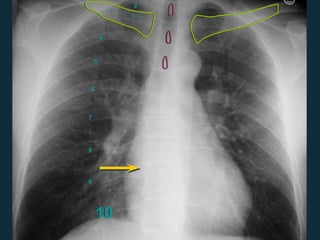

Assess CXR Technical Quality

 Esforço inspiratório

• 9 – 10 costelas posteriores

 Penetração

• Espaço do disco intervertebral torácico

apenas visível

 Posicionamento / rotação

• Extremidade medial das clavículas

equidistantes ao processo espinhoso

10

1

2

3

4

5

6

7

8

9

Inspiratory Effort